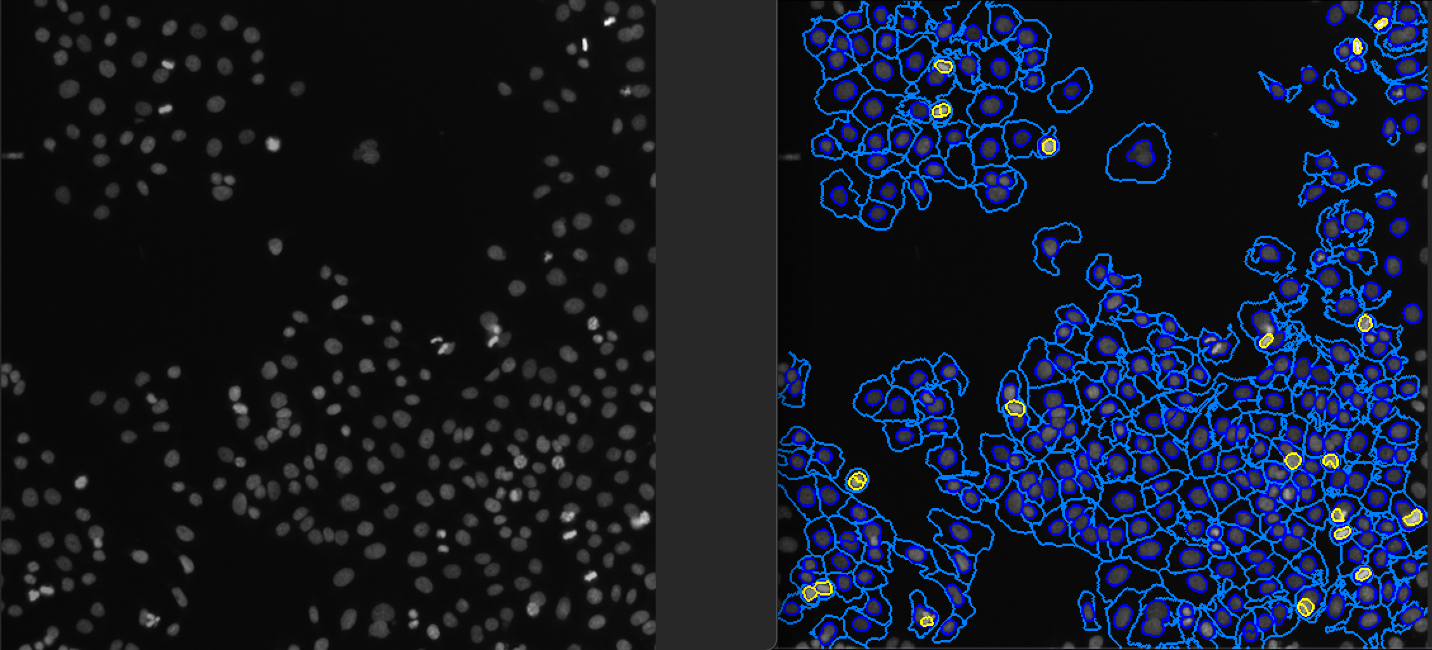

Figure 2 – This diagram shows input cell image before processing (on the left), & output cell image after processing (on the right). Image source: https://github.com/CellProfiler/examples/tree/master/ExampleHuman

- The CellProfiler software within the container processes the image following a defined pipeline. This can involve segmenting the image, extracting features, and other image processing tasks.